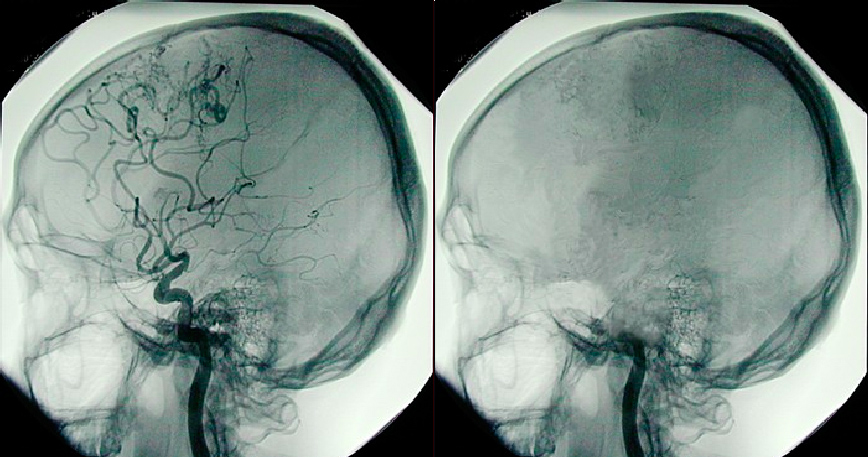

50 anni fa, un comitato ad hoc della scuola medica di Harvard dichiarò che i pazienti in un «coma irreversibile» erano morti da un punto di vista legale ed etico.

Per coma irreversibile, il comitato aveva in mente «individui in coma che non hanno alcuna attività rilevabile sul sistema nervoso centrale». Nel fare questa dichiarazione, il comitato stava cercando di risolvere una serie di questioni etiche e legali che erano sorte dall’avvento della ventilazione a pressione positiva e dalla ricerca sui trapianti di organi vitali.

Eppure Truog osserva anche che «i tentativi di trovare una giustificazione concettuale per collegare questa diagnosi (cioè la morte cerebrale) alla morte del paziente rimangono incompleti». Egli racconta come il neurologo Alan Shewmon abbia dimostrato che virtualmente ogni funzione intrapresa da un corpo vivente sano può essere trasportata da un defunto in un ventilatore.